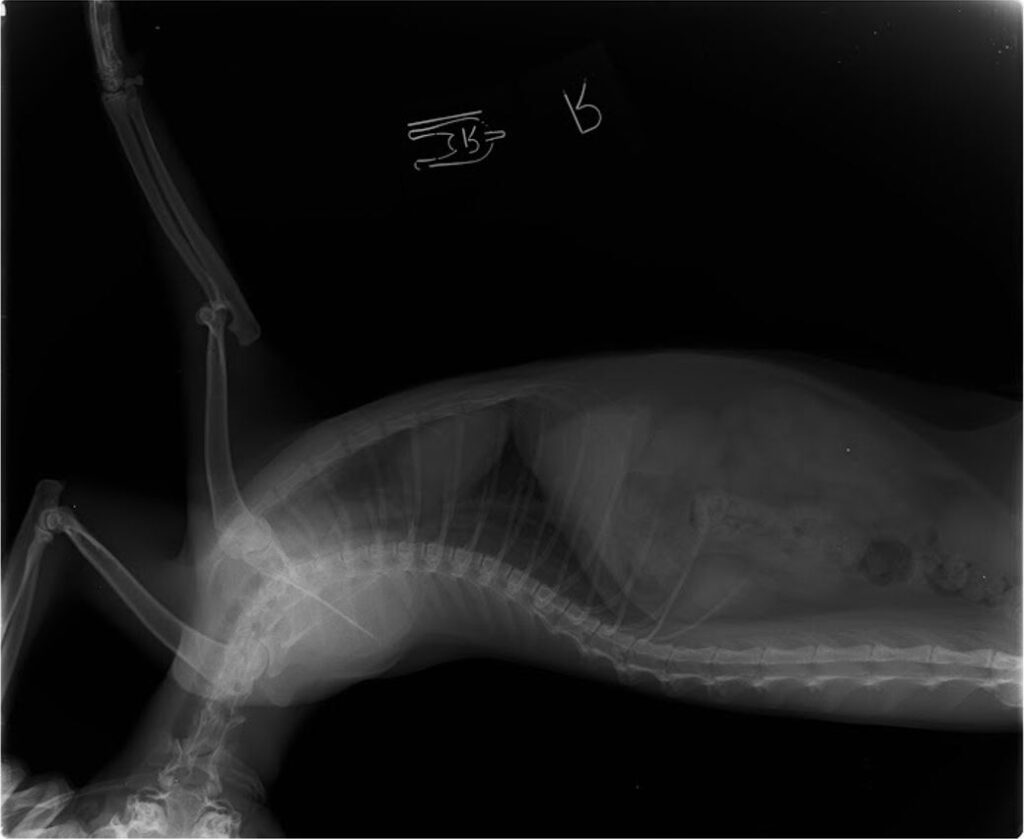

猫肘脱臼 の症例

階段から落下して

右ひじ外側脱臼

診断名:右ひじ外側脱臼

手術例:2020年1月手術

術後1か月経過良く患肢をついている。